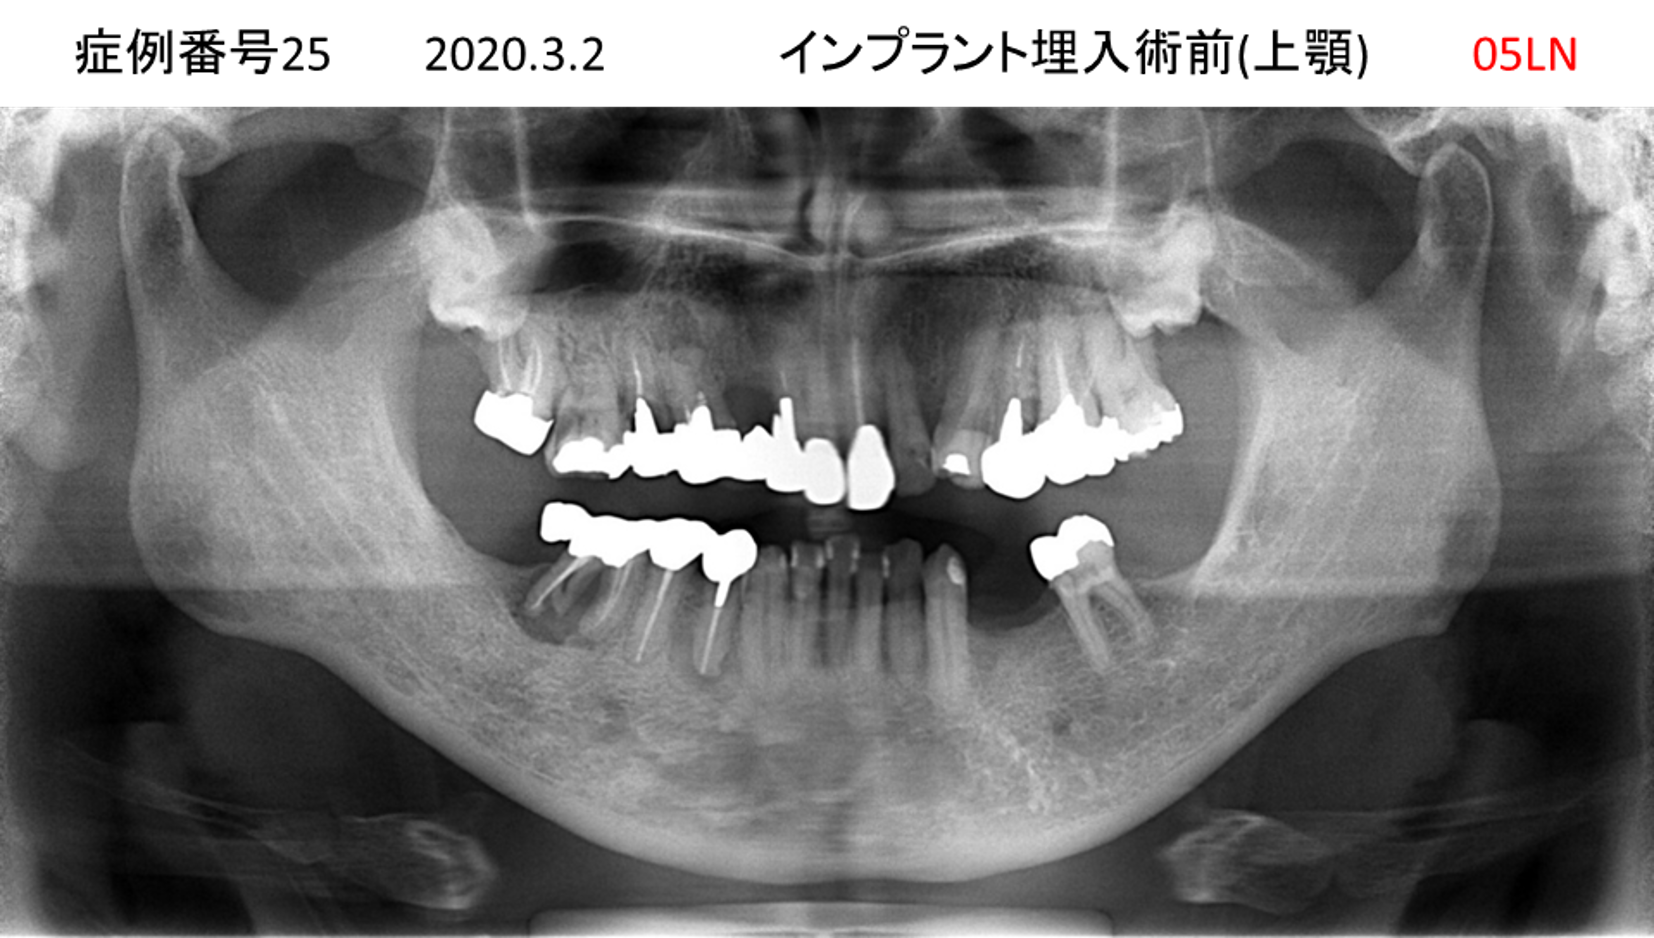

義歯が合わない、噛めない患者様のインプラント症例

| 治療名称 |

インプラントコーヌステレスコープ |

| 治療費用 |

270万円+税 |

| 治療期間 |

4か月 |

| 患者さんの症状(主訴) |

義歯が合わない、噛めない |

| 治療内容 |

インプラント、義歯作製(コーヌステレスコープ) |

| 治療結果 |

しっかり噛めるようになった。見栄えが良くなった。 |

| 治療の注意点(リスク/副作用) |

義歯が壊れた場合、インプラントが壊れた場合は再治療が必要 |